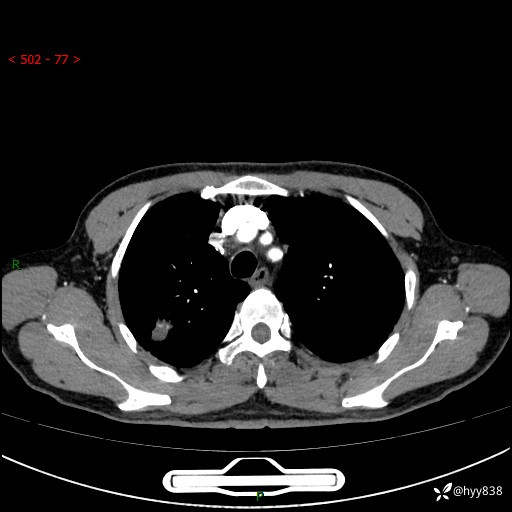

胸部CT平扫+增强